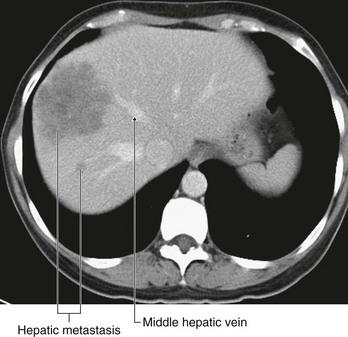

Urinary tract cancer

Most tumors that arise in the kidney are renal cell carcinomas. These tumors develop from the proximal tubular epithelium. Approximately 5% of tumors within the kidney are transitional cell tumors, which arise from the urothelium of the renal pelvis. Most patients typically have blood in the urine (hematuria), pain in the infrascapular region (loin), and a mass.

Renal cell tumors are unusual because not only do they grow outward from the kidney, invading the fat and fascia, but they also spread into the renal vein. This venous extension is rare for any other type of tumor, so, when seen, renal cell carcinoma should be suspected. In addition, the tumor may spread along the renal vein and into the inferior vena cava, and in rare cases can grow into the right atrium across the tricuspid valve and into the pulmonary artery (Figs. 4.142 and 4.143).

image

Fig. 4.142 Tumor in the right kidney growing toward, and possibly invading, the duodenum. Computed tomogram in the axial plane.

Fig. 4.143 Tumor in the right kidney spreading into the right renal vein. Computed tomogram in the axial plane.

Treatment for most renal cancers is surgical removal, even when metastatic spread is present, because some patients show regression of metastases.

Transitional cell carcinoma arises from the urothelium. The urothelium is present from the calices to the urethra and behaves as a “single unit.” Therefore, when patients develop transitional carcinomas within the bladder, similar tumors may also be present within upper parts of the urinary tract. In patients with bladder cancer, the whole of the urinary tract must always be investigated to exclude the possibility of other tumors (Fig. 4.144).

Fig. 4.144 Transitional cell carcinoma in the pelvis of the right kidney. Coronal computed tomogram reconstruction.